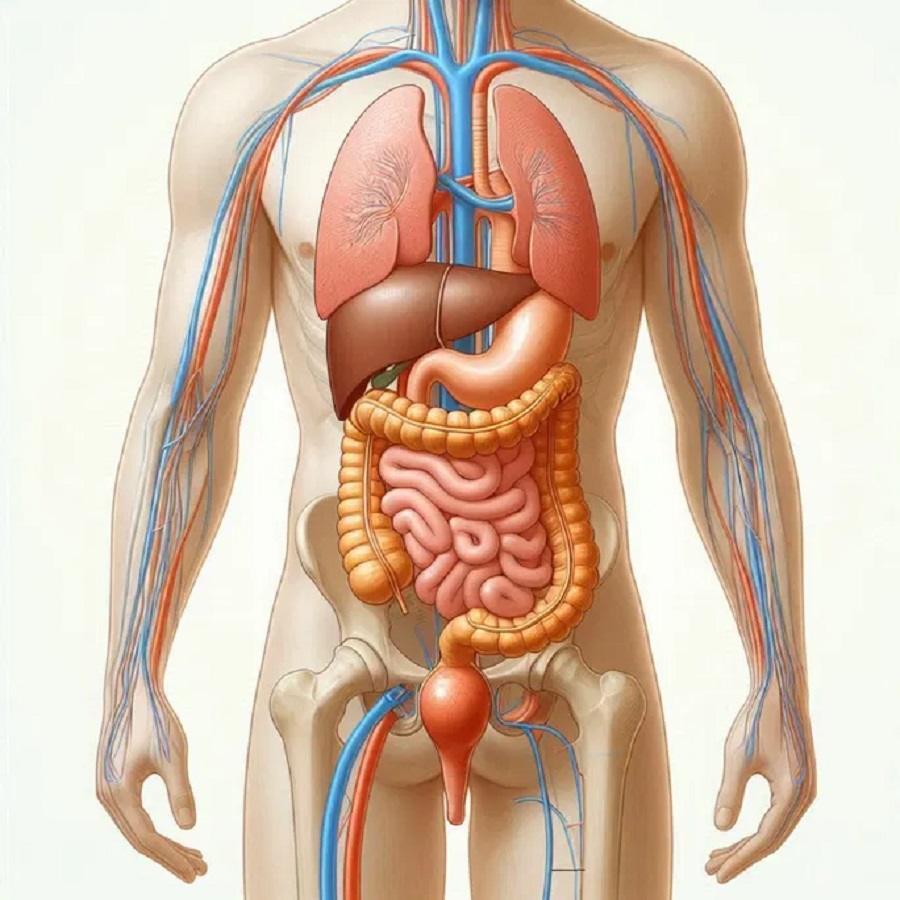

El cuerpo humano es una estructura compleja y fascinante formada por diversos sistemas que trabajan en conjunto para garantizar la supervivencia y el equilibrio interno. Cada uno de estos sistemas está compuesto por órganos, tejidos y células especializadas que realizan funciones esenciales para mantener la vida.

Sistema respiratorio

El sistema respiratorio es responsable del intercambio de gases entre el ambiente y el cuerpo, suministrando oxígeno a las células y eliminando dióxido de carbono.

Componentes

- Vías respiratorias superiores: Incluyen la nariz, faringe y laringe, que filtran y humedecen el aire inhalado.

- Vías respiratorias inferiores: Comprenden la tráquea, los bronquios y los bronquiolos, que conducen el aire hacia los pulmones.

- Pulmones: Contienen alvéolos, pequeñas estructuras donde ocurre el intercambio gaseoso.

- Diafragma y músculos intercostales: Facilitan la respiración al expandir y contraer la cavidad torácica.

Funciones

- Oxigenación: Proporciona oxígeno a la sangre para el metabolismo celular.

- Eliminación de dióxido de carbono: Expulsa este gas como subproducto del metabolismo.

- Regulación del pH sanguíneo: Controla los niveles de dióxido de carbono para mantener un equilibrio ácido-base.

- Protección: Las mucosas y cilios filtran partículas y microorganismos.

Sistema digestivo

Elsistema digestivo descompone los alimentos en nutrientes que el cuerpo puede absorber y utiliza para obtener energía, crecimiento y reparación de tejidos.

Componentes

- Tracto gastrointestinal: Incluye boca, esófago, estómago, intestinos delgado y grueso, recto y ano.

- Órganos accesorios: Hígado, vesícula biliar y páncreas, que producen enzimas y bilis para la digestión.

Funciones

- Ingestión: Introducción de alimentos en la boca.

- Digestín mecánica y química: Descomposición de alimentos mediante masticación y enzimas.

- Absorción: Transporte de nutrientes desde los intestinos hacia la sangre o linfa.

- Eliminación: Expulsión de desechos no digeridos a través del ano.

Sistema Excretor

El sistema Excretor elimina desechos líquidos y regula el equilibrio de agua y electrolitos en el cuerpo.

Componentes

- Riñones: Filtran sangre para formar orina.

- Uretra y uréteres: Conducen la orina hacia la vejiga.

- Vejiga urinaria: Almacena orina hasta su eliminación.

Funciones

- Eliminación de desechos: Excreta productos metabólicos.

- Regulación del equilibrio hídrico: Mantiene niveles adecuados de agua y sal.

- Control del pH: Ajusta la acidez sanguínea.